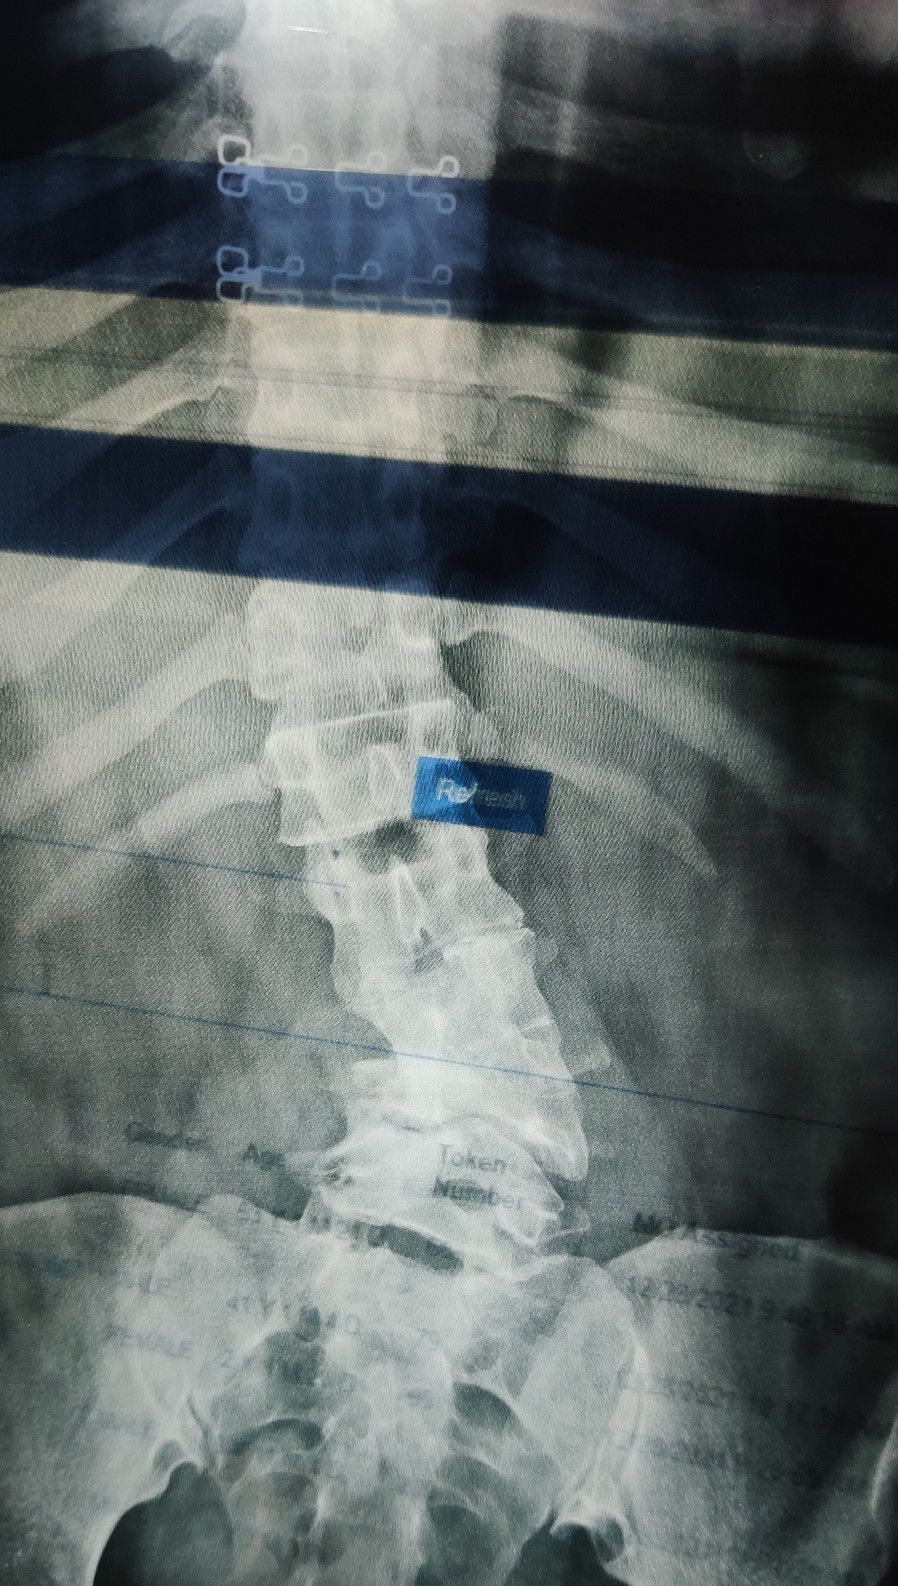

Scoliosis

Xray

Ortho